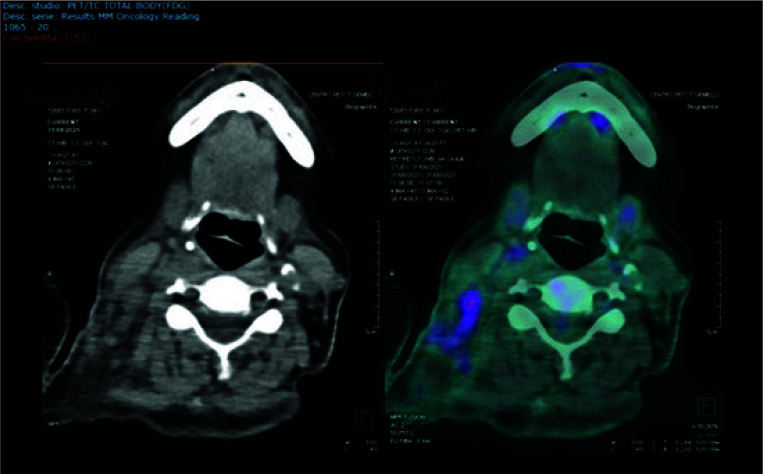

Abstract Image